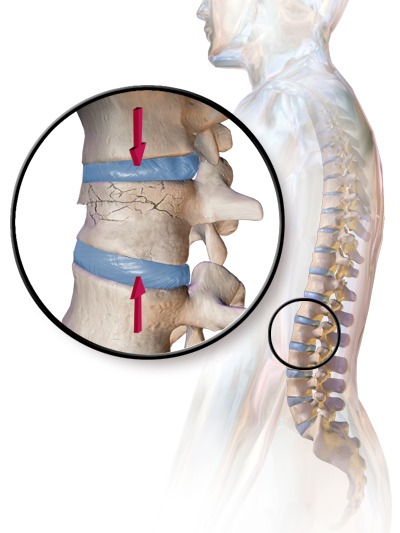

تنگی کانال نخاعی

تنگی کانال نخاعی حالتی است که در آن فضای اطراف نخاع باریک میشود و فشار زیادی بر اعصاب وارد میکند. این بیماری یکی از علل شایع انواع کمردرد در سنین بالاست. بیماران معمولاً هنگام راه رفتن دچار درد و بیحسی پاها میشوند.

درمان اولیه شامل فیزیوتراپی، دارو و تمرینات تقویتی است. در موارد پیشرفته، جراحی برای آزادسازی کانال نخاعی انجام میشود. پس از جراحی نیز فیزیوتراپی در بازتوانی نقش مهمی دارد.